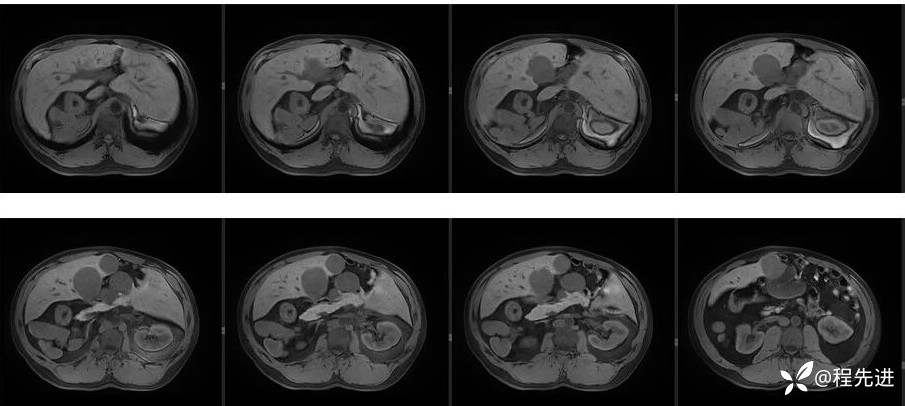

辅助检查:上腹部平扫+增强扫描提示:肝脏、脾脏、胰腺 、胃十二指肠左右倒置,脾脏形态失常,呈分叶团块状,考虑发育变异。肝左右交界区多发肿块,考虑:上皮样血管内皮瘤可能性大,或转移瘤?其它?请结合临床。脂肪肝。肝门胆管局限性扩张。胆囊折叠,壁稍增厚,慢性炎症?胰腺下方椭圆形结节,副脾?

影像检查